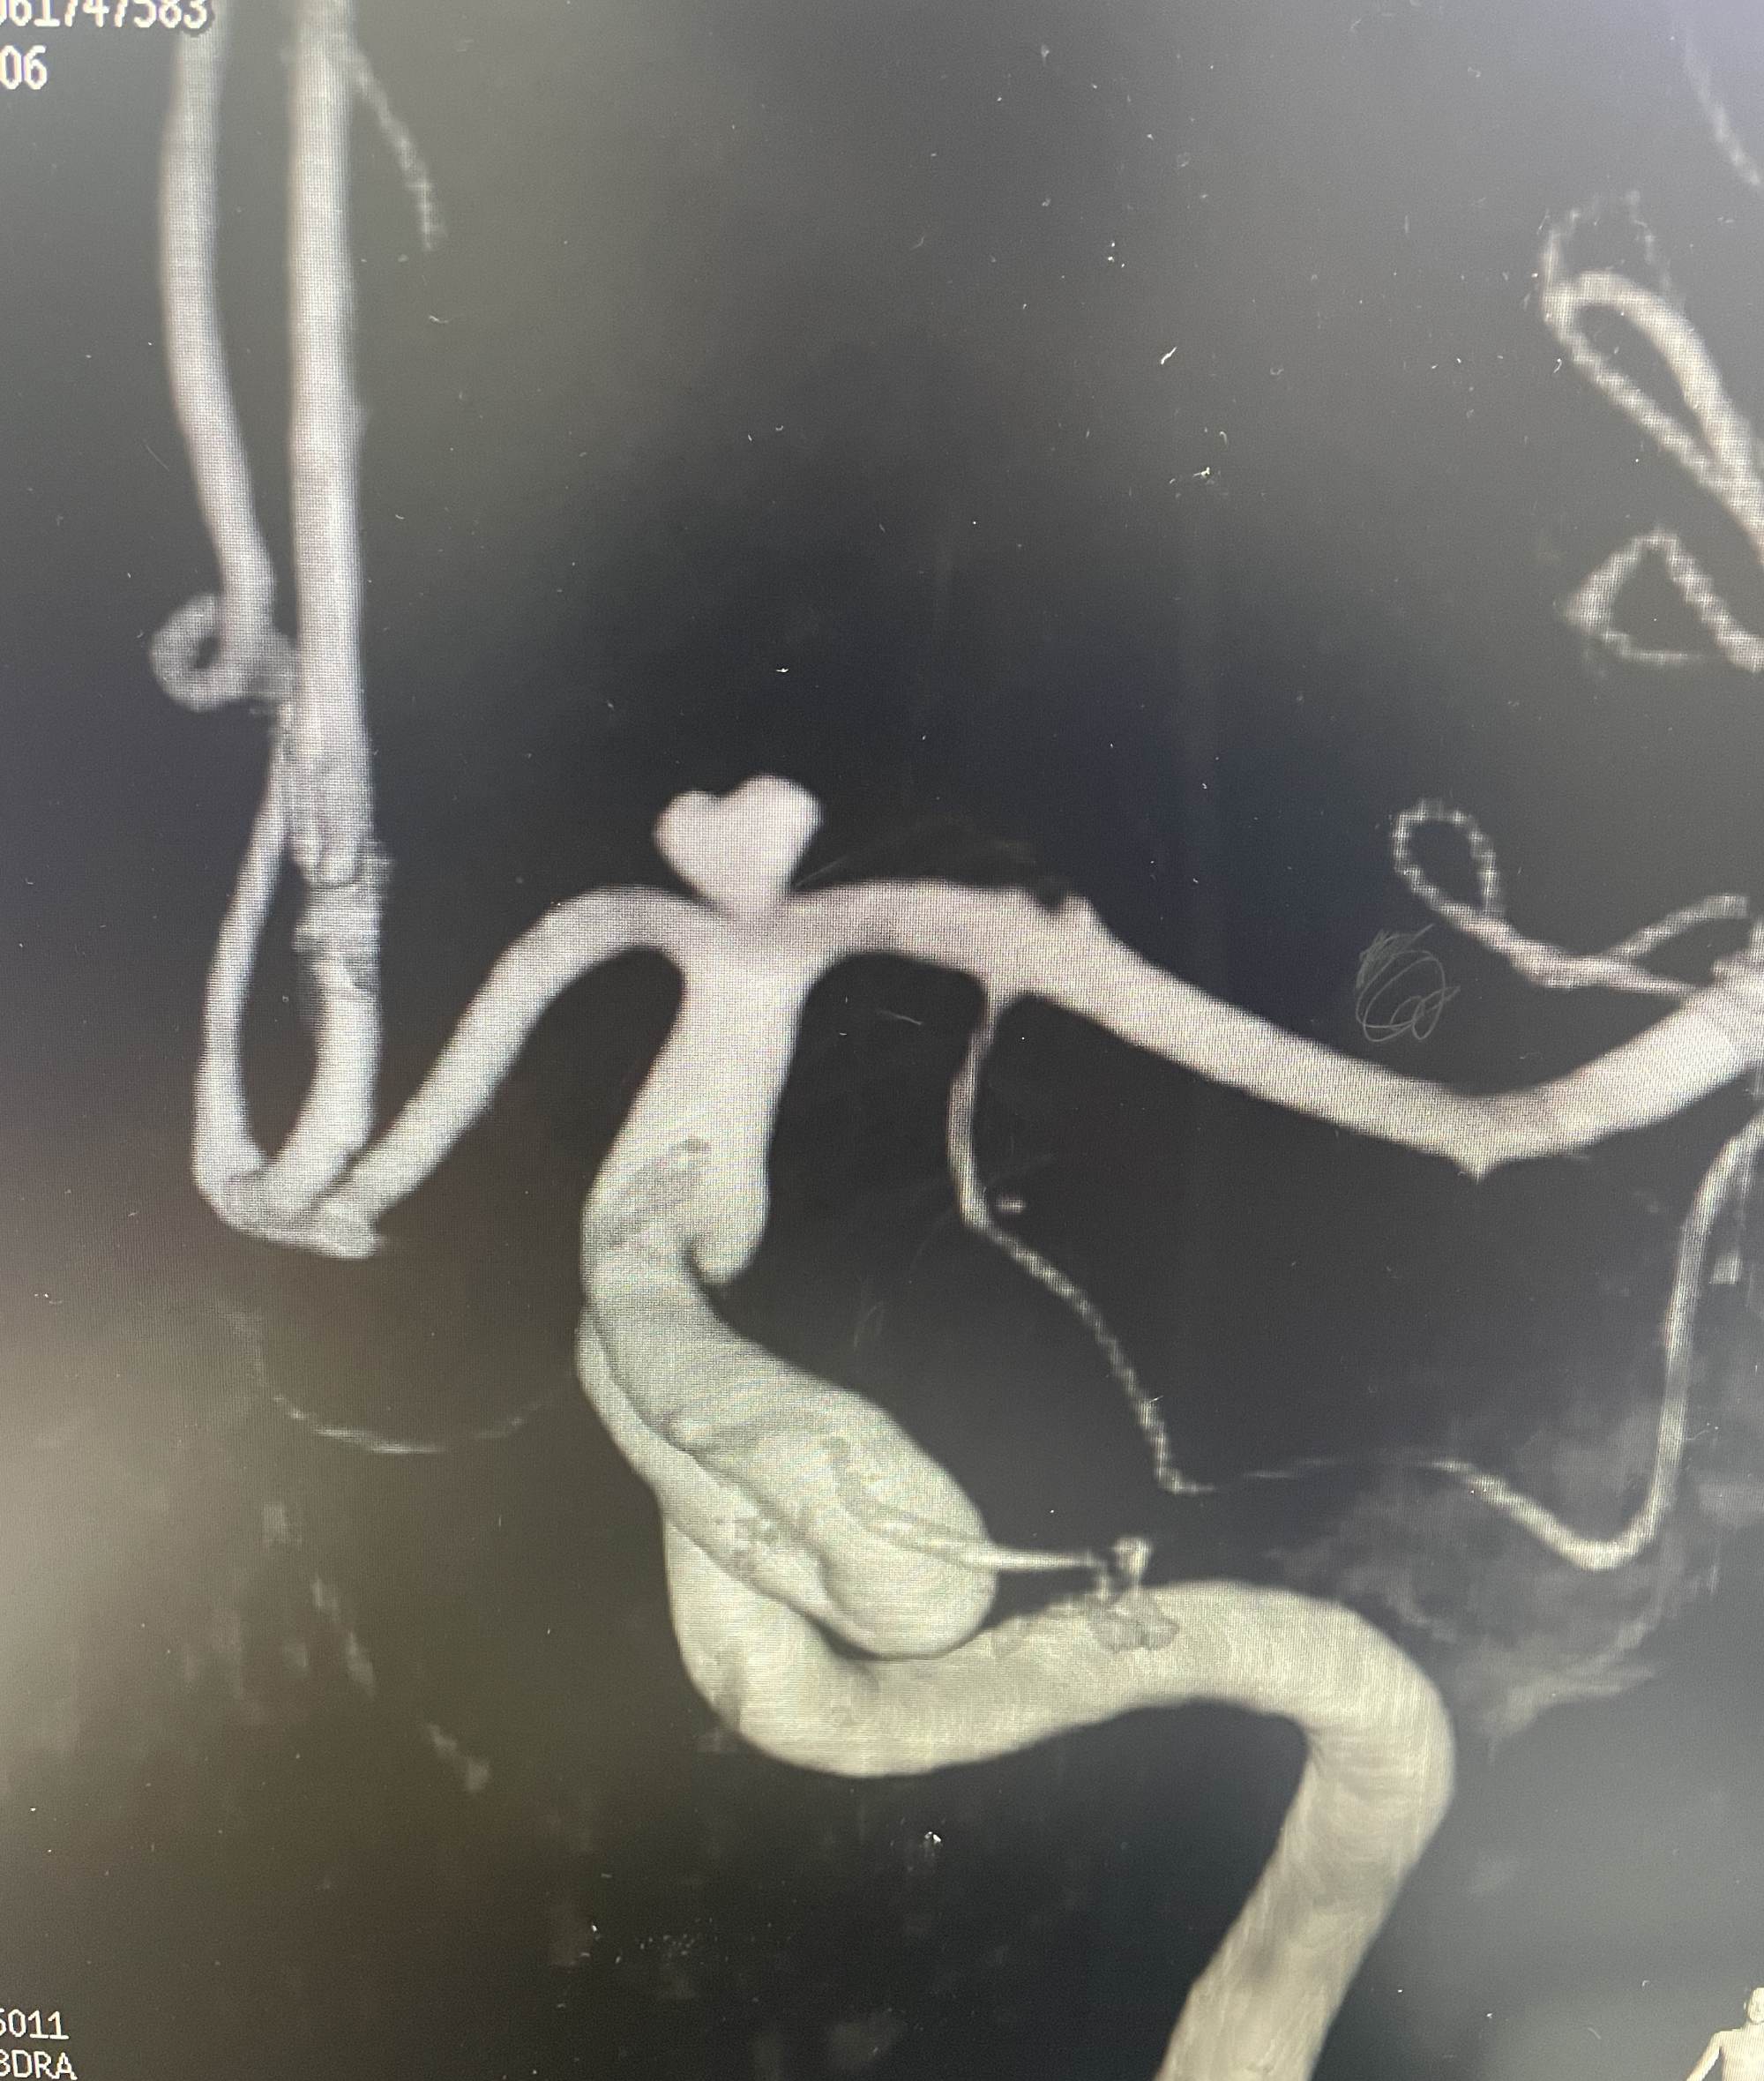

DSA提示右侧后交通动脉瘤,左侧颈内动脉末端动脉瘤,左侧后交通圆锥,左侧海绵窦夹层动脉瘤。

下面这个动脉瘤像不像一颗爱心,可是它很“凶残”。随时可能破裂出血,危急患者生命。

我们术中先解决右侧后交通责任动脉瘤,再解决左侧颈内动脉末端以及海绵窦夹层动脉瘤,手术顺利,动脉瘤消失,可谓一箭三雕🐮!